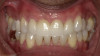

Fig 3. Candidates for hybrid teledentistry include patients with minor (Fig 2), moderate (Fig 3), and advanced crowding (Fig 4).

Figure 3